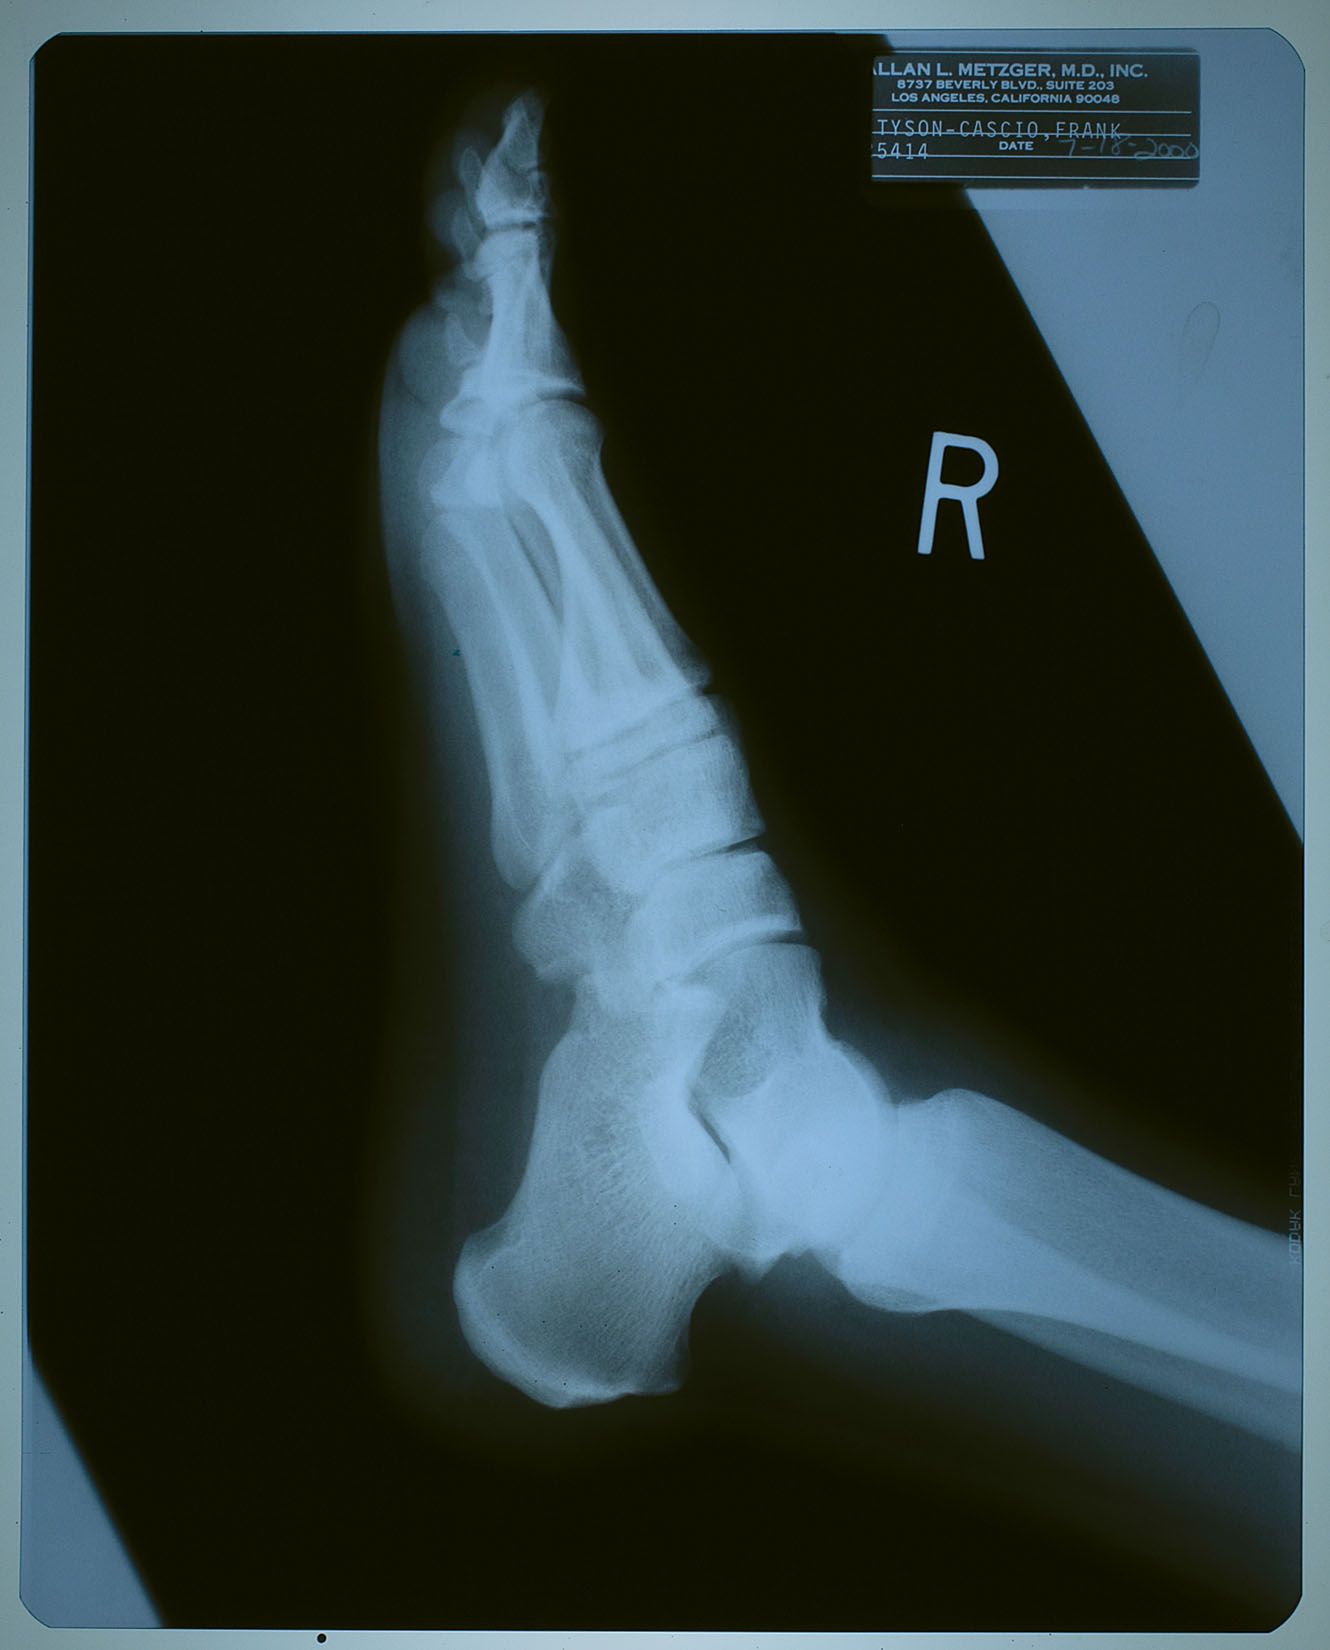

2000年7月18日、ネバーランドで子供たちと遊んでいて

怪我をした時に撮ったX線写真。

名前が 「タイソン-カシオ,フランク」 になっているけども、

カシオ本を読んだ御仁はお判りでしょう。

"タイソン" というのは、前年からマイケルの代理人を務めるようになった

フランク・カシオ君の仕事上での通名。

診療所などでは、マイケルがプライバシー面からフランク君の名を使う事もあったそう。

松葉杖を持っていないし、大事には至らなかった様子。

ただし、よく見ると靴はサンダルっぽいので、捻挫ぐらいにはなっちゃったかも?